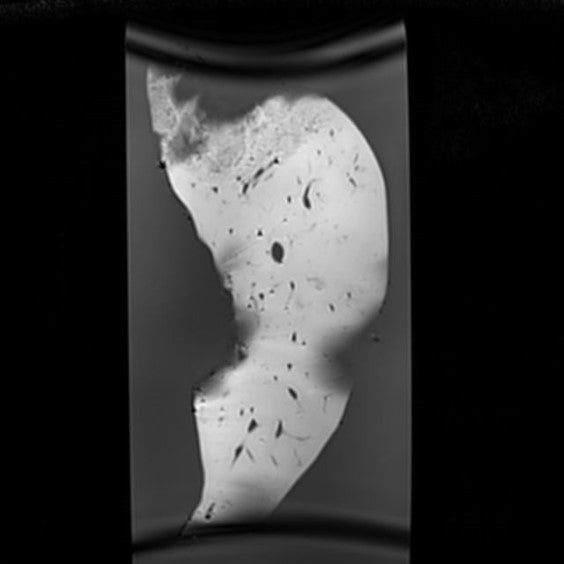

Liver - Cyst